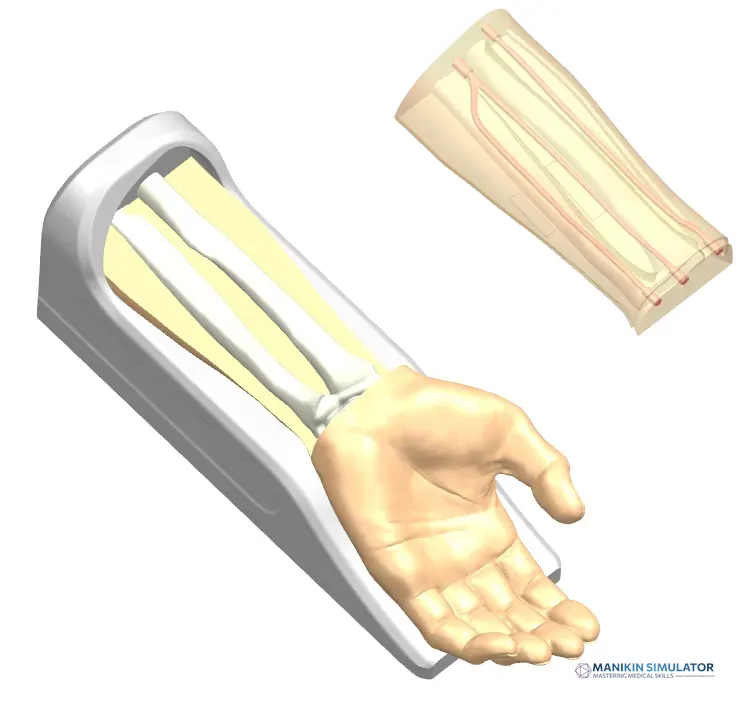

Radial Artery Puncture Operation Model (Ultrasound Guided) adalah simulator lengan bawah untuk pelatihan kanulasi arteri radialis dengan panduan USG. Arteri radialis dibuat berdasarkan data CT manusia.

Material komposit khusus memungkinkan visualisasi arteri yang jelas di layar USG *real-time*. Memberikan sensasi ‘tembus’ (*breakthrough*) yang realistis saat jarum menembus dinding arteri.

Drawing of Radial Artery Puncture Operation Model (Ultrasound-Guided)